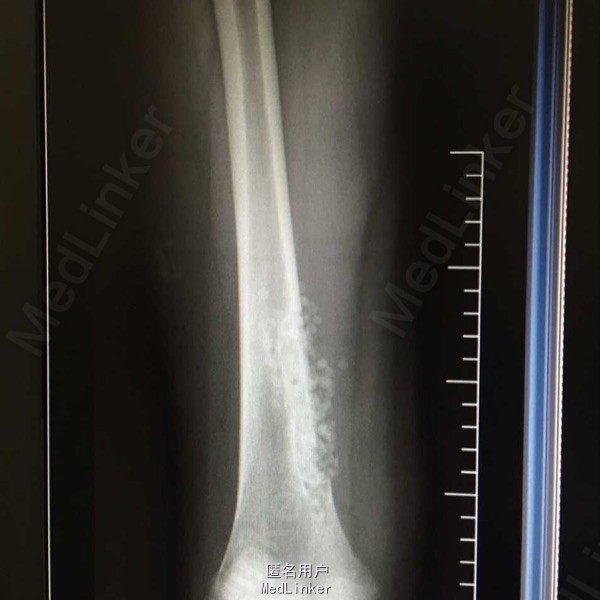

患者,女,13岁,长时间走路后出现右股部下段疼痛,呈间断性,偶然有夜间痛

CT结果为右侧股骨皮质内可见一条片状骨质缺损区,呈软组织样密度影,范围约12*8*48cm,其边缘可见条状硬化,病变长轴与股骨长轴一致,考虑纤维性骨皮质破损,X线示:右股骨下端距关节上方约6cm处可见骨质密度减低影,成分房状,边界可见钙化影。

术后病理报告结为:”右股骨下段“小块增生纤维组织伴含铁血黄素沉着,片内提示结合临床及影像学考虑,干骺端纤维缺损或非骨化纤维瘤。